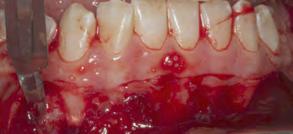

Figura 4. A. Marcaje con bisturí de la muestra a tomar. B. Lecho quirúrgico de la muestra tomada. C. Afronte de la herida. A B C

Estudios tomográficos en los cuales se observa tumoración expansiva a piso nasal de 3 centímetros de diá metro aproximadamente isodensa a tejidos blandos en zona de pala dar blando (Figura 3A y 3B). Motivo por el cual se decidió realizar biopsia incisional (Figura 4A , 4B y 4C) obte niendo un diagnóstico de Adenocar cinoma de células basales en paladar blando (Figura 5) con el cual se rea lizó referencia al centro oncológico naval para su seguimiento y trata miento. Actualmente se encuentra en tratamiento de quimioterapia.

Paciente Figura 1. Fotografía clínica frontal. Figura 2. Con aumento de volumen y úlcera en paladar blando.